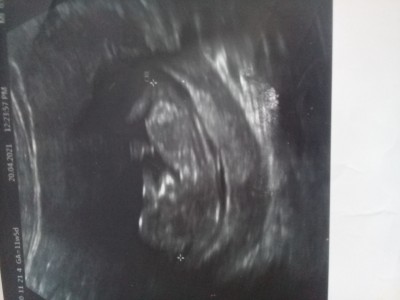

Merhaba hanımlar ben 25 haftalık hamileyim şu ana  kadar sürekli doktora gittim ama bebeğimin cinsiyetini tam olarak öğrenemedim sizce bebeğimin cinsiyeti hakkında tahminde bulunabilirmisiniz sizce ne geçiyor içinizden nub teorisine gore ne oluyor

Gebelik haftası 25 haftalik

Kız bence canım sağlıkla gelsin

Bence erkek gibi Rabbim sağlıkla kucağına almayı nasip etsin :)

Büyük bir ihtimalle erkek bebek